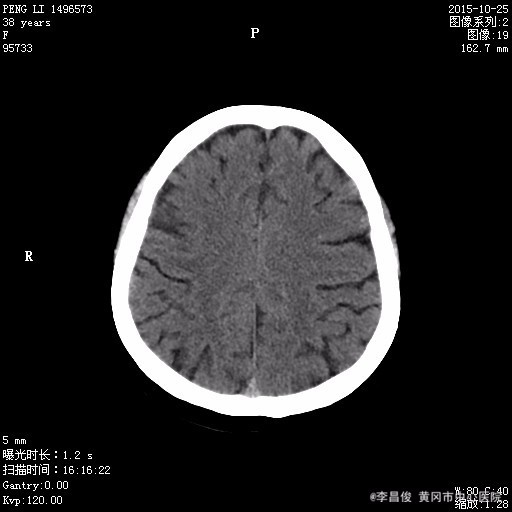

患者,女,38岁,2015年10月25日中午十二时赴酒宴时突发意识障碍,四肢抽搐,口唇发绀,双眼向上凝视,持续约十分钟后人意识逐渐清楚,伴恶心呕吐数次,遂急送我院120,行头部CT:脑萎缩,建议结合临床必要时行MRI检查,并以"癫痫"收住我科。 起病来,患者精神食欲睡眠差,大小便正常,体力下降,体重未有明显改变。 既往胃溃疡病史,有多次摔伤史,每天饮啤酒4-5瓶,饮白酒一斤;饮酒20年,每天吸烟20支,20年。

体格检查:BP130/90mmHg、 HR90次/分、 R16次/分, T36.5℃ 神清,精神欠佳,步入病房,查体合作。全身皮肤巩膜无明显黄染,结膜充血,全身多处淤青。颈软,甲状腺未及,双肺呼吸音清,未闻及明显干湿啰音,心律齐,各瓣膜区未闻及明显病理性杂音,腹软,肝脾肋下未及,双下肢不肿。 专科情况:神清,双侧瞳孔等大等圆,对光反射灵敏,四肢肌力肌张力正常,双侧病理征阴性,四肢有震颤。 辅助检查结果: 2015.10.25 头部CT:脑萎缩,建议结合临床必要时行MRI检查。2015.10.27 头部MRI:1.脑白质疏松;2.小脑萎缩;3.筛窦炎。 2015.10.26 血常规:白细胞 9.08*10^9/L,红细胞 3.47*10^12/L,血红蛋白 132g/L,血小板 88*10^9/L,中性粒细胞比率 92.2%;肝肾功能血糖血脂电解质:谷丙转氨酶 65.1U/L,谷草转氨酶 139.4U/L,尿酸 644.2umol/L,葡萄糖 8.16mmol/L,总胆固醇 9.93mmol/L,高密度脂蛋白胆固醇 3.87mmol/L,低密度脂蛋白胆固醇 4.86mmol/L,同型半胱氨酸 58.21umol/l;肌肉酶谱:磷酸肌酸激酶 309.1U/L,乳酸脱氢酶 397U/L;